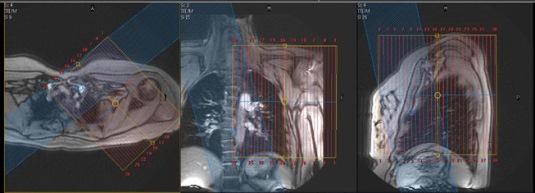

| AXIAL | T1 FS | TSE | 4mm | 1mm | SPIR | 20cm | Same as pre |

| COR | T1 FS | TSE | 4mm | 1mm | SPIR | 22cm | Same as pre |

| SAG | T1 FS | TSE | 4mm | 1mm | SPIR | 22cm | Same as pre |